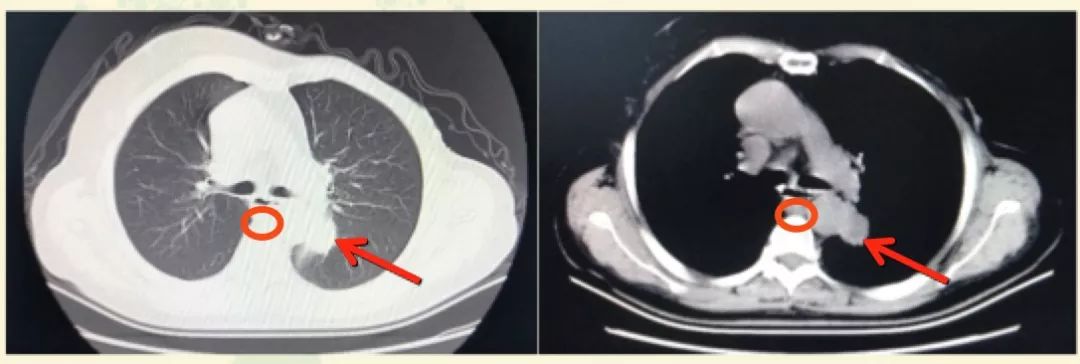

2018年12月起,患者进食梗咽感并进行性加重至无法进食。CT检查发现纵隔淋巴结转移、肺转移、左肾上腺转移。请消化内科会诊,认为无法进食系纵隔淋巴结转移压迫食管所致,遂行食管扩张术,鼻饲管全流质饮食。超声检查示左侧锁骨上窝低回声结节3.18×2.54cm,考虑淋巴结转移。CA15-3为80.7U/mL。左侧锁骨上淋巴结穿刺活检,病理示:小灶转移性腺癌,符合转移性乳腺癌,免疫组化:ER(-)PR(-)HER2(3+)。患者拒绝肺穿刺病理学检查。

图1. 2018年12月胸部CT检查

于2019年2月1日起行“曲妥珠单抗+紫杉醇(qw*3)方案治疗两周期,2019年3月14日复查,超声示左锁骨上窝结节1.73×1.70cm,较前缩小。胸部CT示左纵隔淋巴结及左肺下叶背段转移瘤与前片比较明显缩小。CA15-3降至52.18U/ml。

图2. 治疗前后胸部CT对比